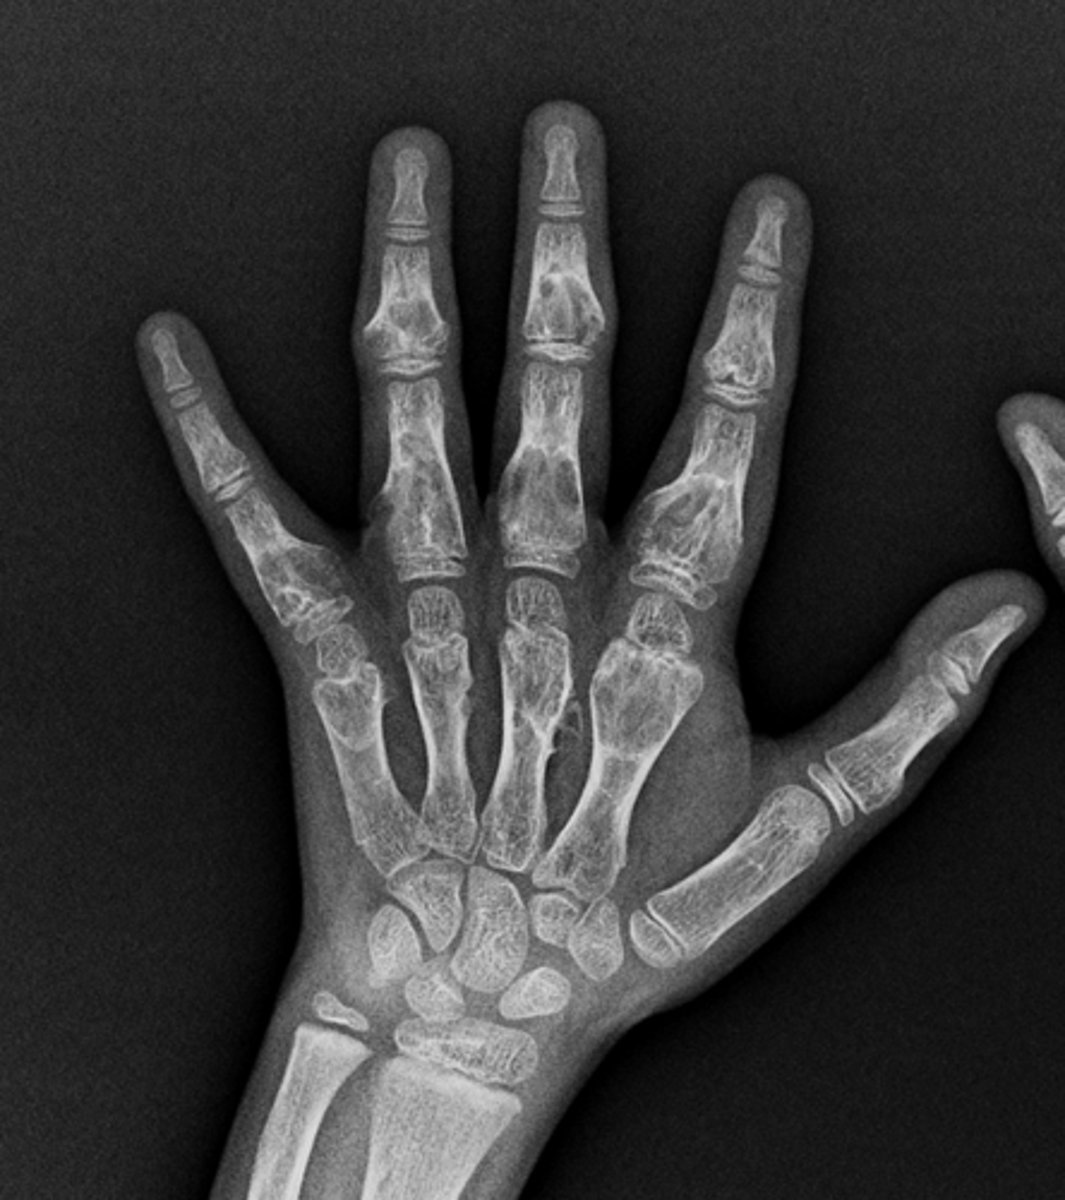

- Head of 5th metacarpal

• Cortical thinning

• Lucency in head

• Pathologic fracture

• Stippled calcification

• Cartilaginous matrix

• Geographic

• Short zone of transition

Describe the lesion

Solitary enchondroma

Fracture

What complication has occurred?